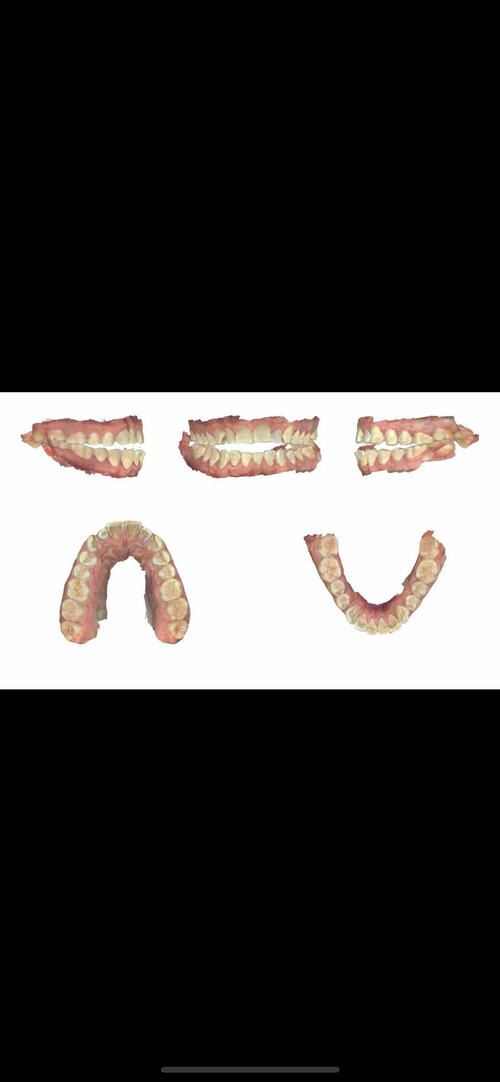

I asked if it were possible to advance both jaws forward at an even amount without decomp and he said that’s possible but risky, and that I would “be responsible” for anything that happens afterwards such as bite issues.

I asked if it were possible to advance both jaws forward at an even amount without decomp and he said that’s possible but risky, and that I would “be responsible” for anything that happens afterwards such as bite issues.